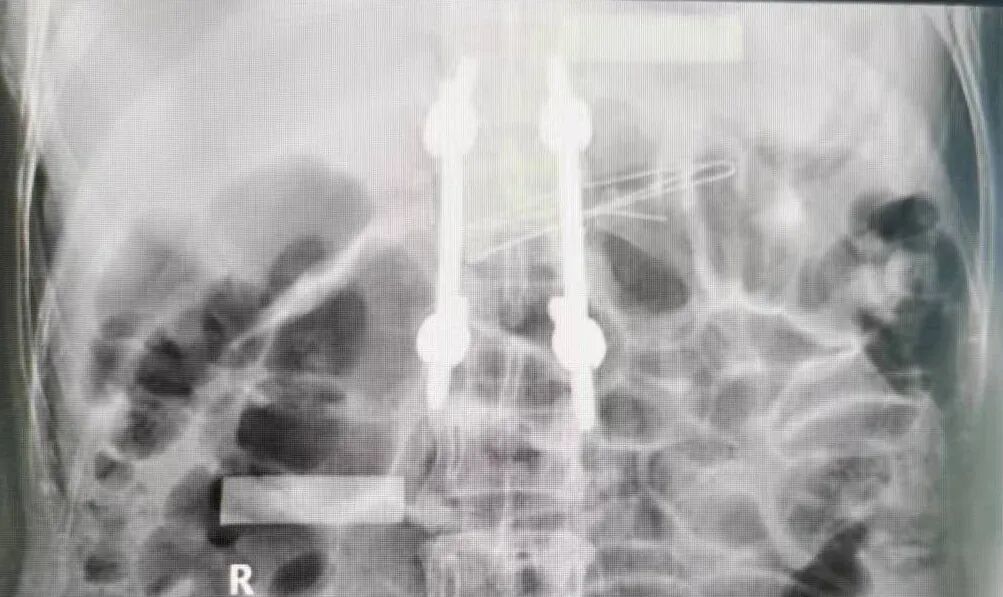

在麻醉科的通力协作下,由陈龙潭医生主刀,张林医生协助,为患者成功实施了微创经皮椎弓根螺钉内固定手术。术中,两位医生紧密配合,熟练运用C臂机透视定位,经皮肤打孔植入钉棒内固定系统,术后骨折复位满意,螺钉固定位置良好,椎体高度恢复满意。

整个手术用时短,出血量少,患者术后安返病房。术后在护理团队的精心护理下,患者顺利康复出院。